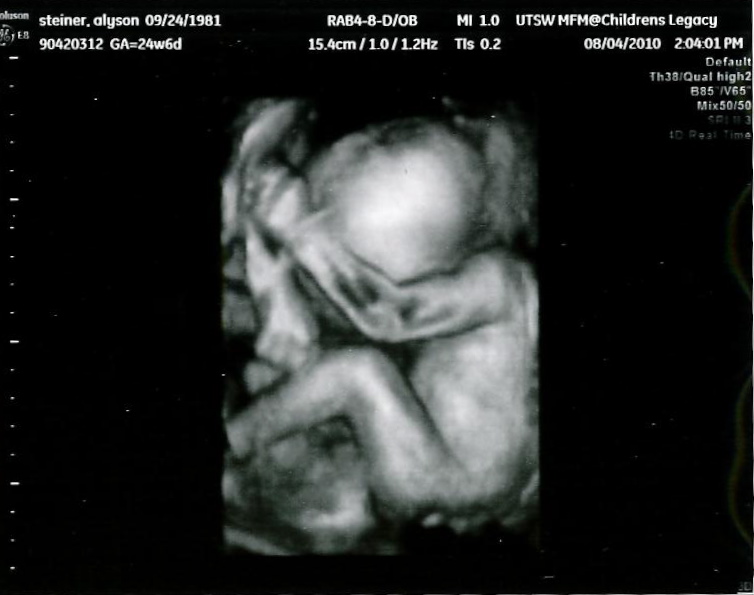

By four, I was out in the living room, trying to get comfy, and Justin came out. He was obviously worried, saw that i was worried, and was the smart one and said, "Let's go. It will at least put your mind at ease." So we went off to the hospital at 5:45, and they were able to hook me up to the monitors right away and see that my stinking uterus was indeed having some contractions and uterine irritations. The boys' heartbeats looked and sounded great, though. They contacted my high risk doctor, and he came by around 1:30. He did an ultrasound, and my cervix and TAC are long, closed, and holding well. The boys look great, but his big concern is that with a TAC, contractions that don't stop and only get worse could lead to a ruptured uterus. Not a good thing at all, but he doesn't think my contractions are that strong yet. He just wants them to stop.